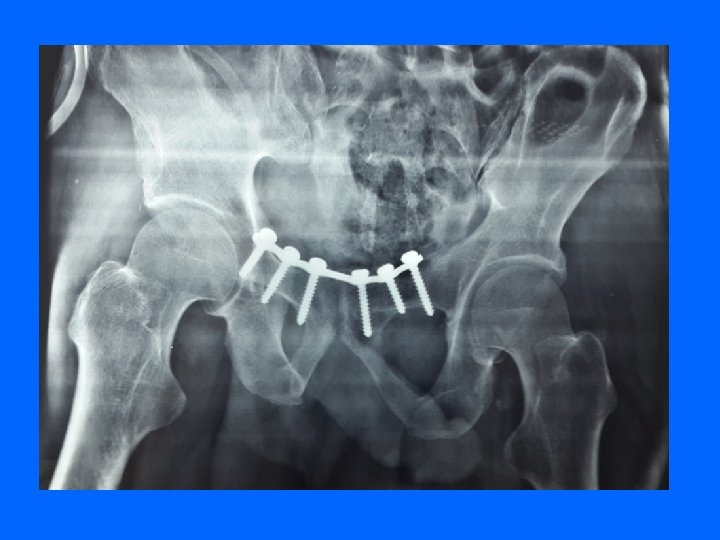

Trt Chirurgical L'ostéosynthèse : obtenir une réduction anatomique et une stabilité immédiate, qui évite un alitement prolongé. Ostéosynthèse par plaques vissées sur la symphyse pubienne ou par vis ilio-sacrées.

Fixateur externe : stabilise rapidement et sans ouvrir les disjonctions antérieures et postérieures. permet de traiter tout de suite les lésions associées